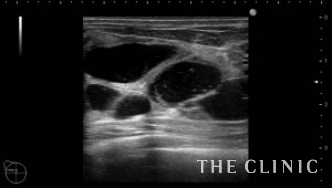

この方は2ヵ月前にヒアルロン酸注入を受けられていますが、除去したいとのご希望でご来院されました。エコーにて、乳腺下に一塊のものと蜂の巣状、皮下にも蜂の巣状のヒアルロン酸のしこりを確認しました。

しこりを穿刺し、ヒアルロニダーゼを注入して吸引除去します。